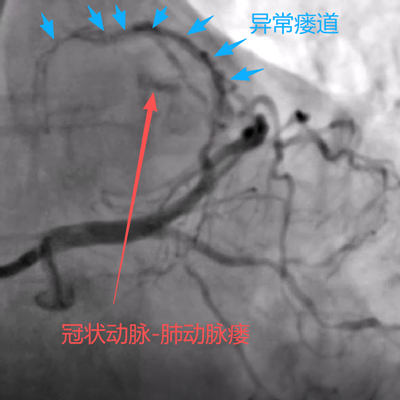

据悉,患者刘某近一年来反复出现胸闷、气短等症状,严重影响了日常生活。她来到县人民医院心血管内科就诊,经过详细检查,并完善冠状动脉造影检查,确诊其患有“冠状动脉-肺动脉瘘”。(如下图)

手术当日,在数字减影血管造影(DSA)设备的精确引导下,手术团队通过患者手腕部仅有米粒大小的穿刺点,将一根细如发丝的微导管,犹如“穿针引线”般精准送达深藏在心脏的异常瘘管内。随后,通过导管将栓塞物质置于瘘管的关键部位,成功实现了对异常通道的“精准封堵”。术后即刻造影显示,异常血流分流完全消失,被“盗走”的血液重新回到了正常的冠脉轨道,手术取得圆满成功。(如下图)